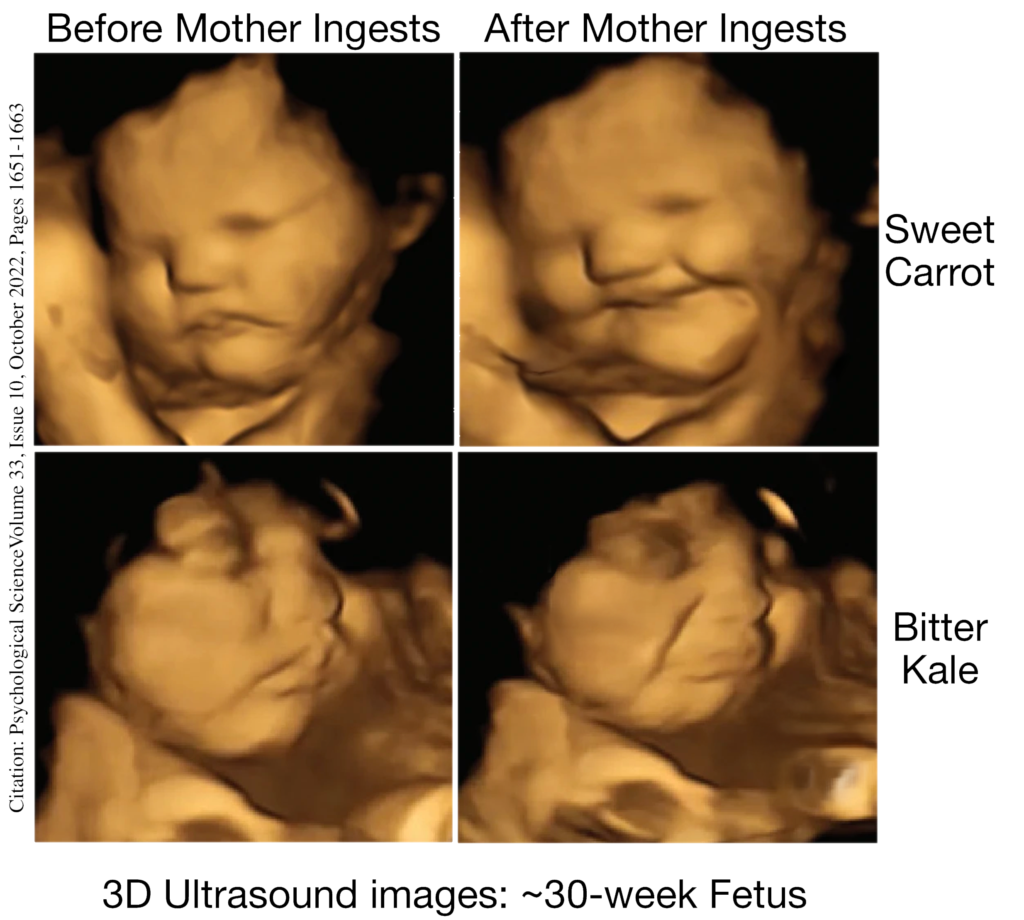

Weeks 17–20: Senses and Reactions

- The baby’s nervous system (brain and nerves) continues to develop, and it starts to react to light and sound.

- The baby’s ears are fully formed, so it can even start hearing sounds like the mother’s heartbeat and voice!

- Data Interpretation: Using the life-size anatomical models and ultrasound images provided, what key changes can you identify in fetal organ systems during the second and third trimesters, and how do these changes prepare the fetus for survival after birth?”

During the second and third trimesters, you’ll notice that major organ systems such as the lungs, brain, and heart continue to mature. For example, the lungs develop air sacs for breathing, the brain increases in size and complexity, and the heart grows stronger. These developments, along with an overall increase in size and weight shown in the models, prepare the fetus for the challenges of life outside the womb. - Critical Thinking: Why might a baby born prematurely at the end of the sixth month have a chance to survive, and which organ systems do you think are most critical for this early viability?

A baby born at the end of the sixth month can survive because key organ systems, especially the lungs, have developed enough to allow breathing, albeit with medical support. Additionally, a developing heart and maturing brain contribute significantly to viability, while modern medical interventions further support these systems until the baby is fully mature. - Real-World Application: How does using ultrasound technology during the later stages of pregnancy benefit both expectant parents and medical professionals in monitoring fetal development?

Ultrasound technology allows doctors to non-invasively track the growth and development of the fetus in real time, identifying any potential issues early. This monitoring provides expectant parents with reassurance and helps medical professionals adjust prenatal care to ensure a safe delivery, illustrating the vital role of technology in modern obstetrics.